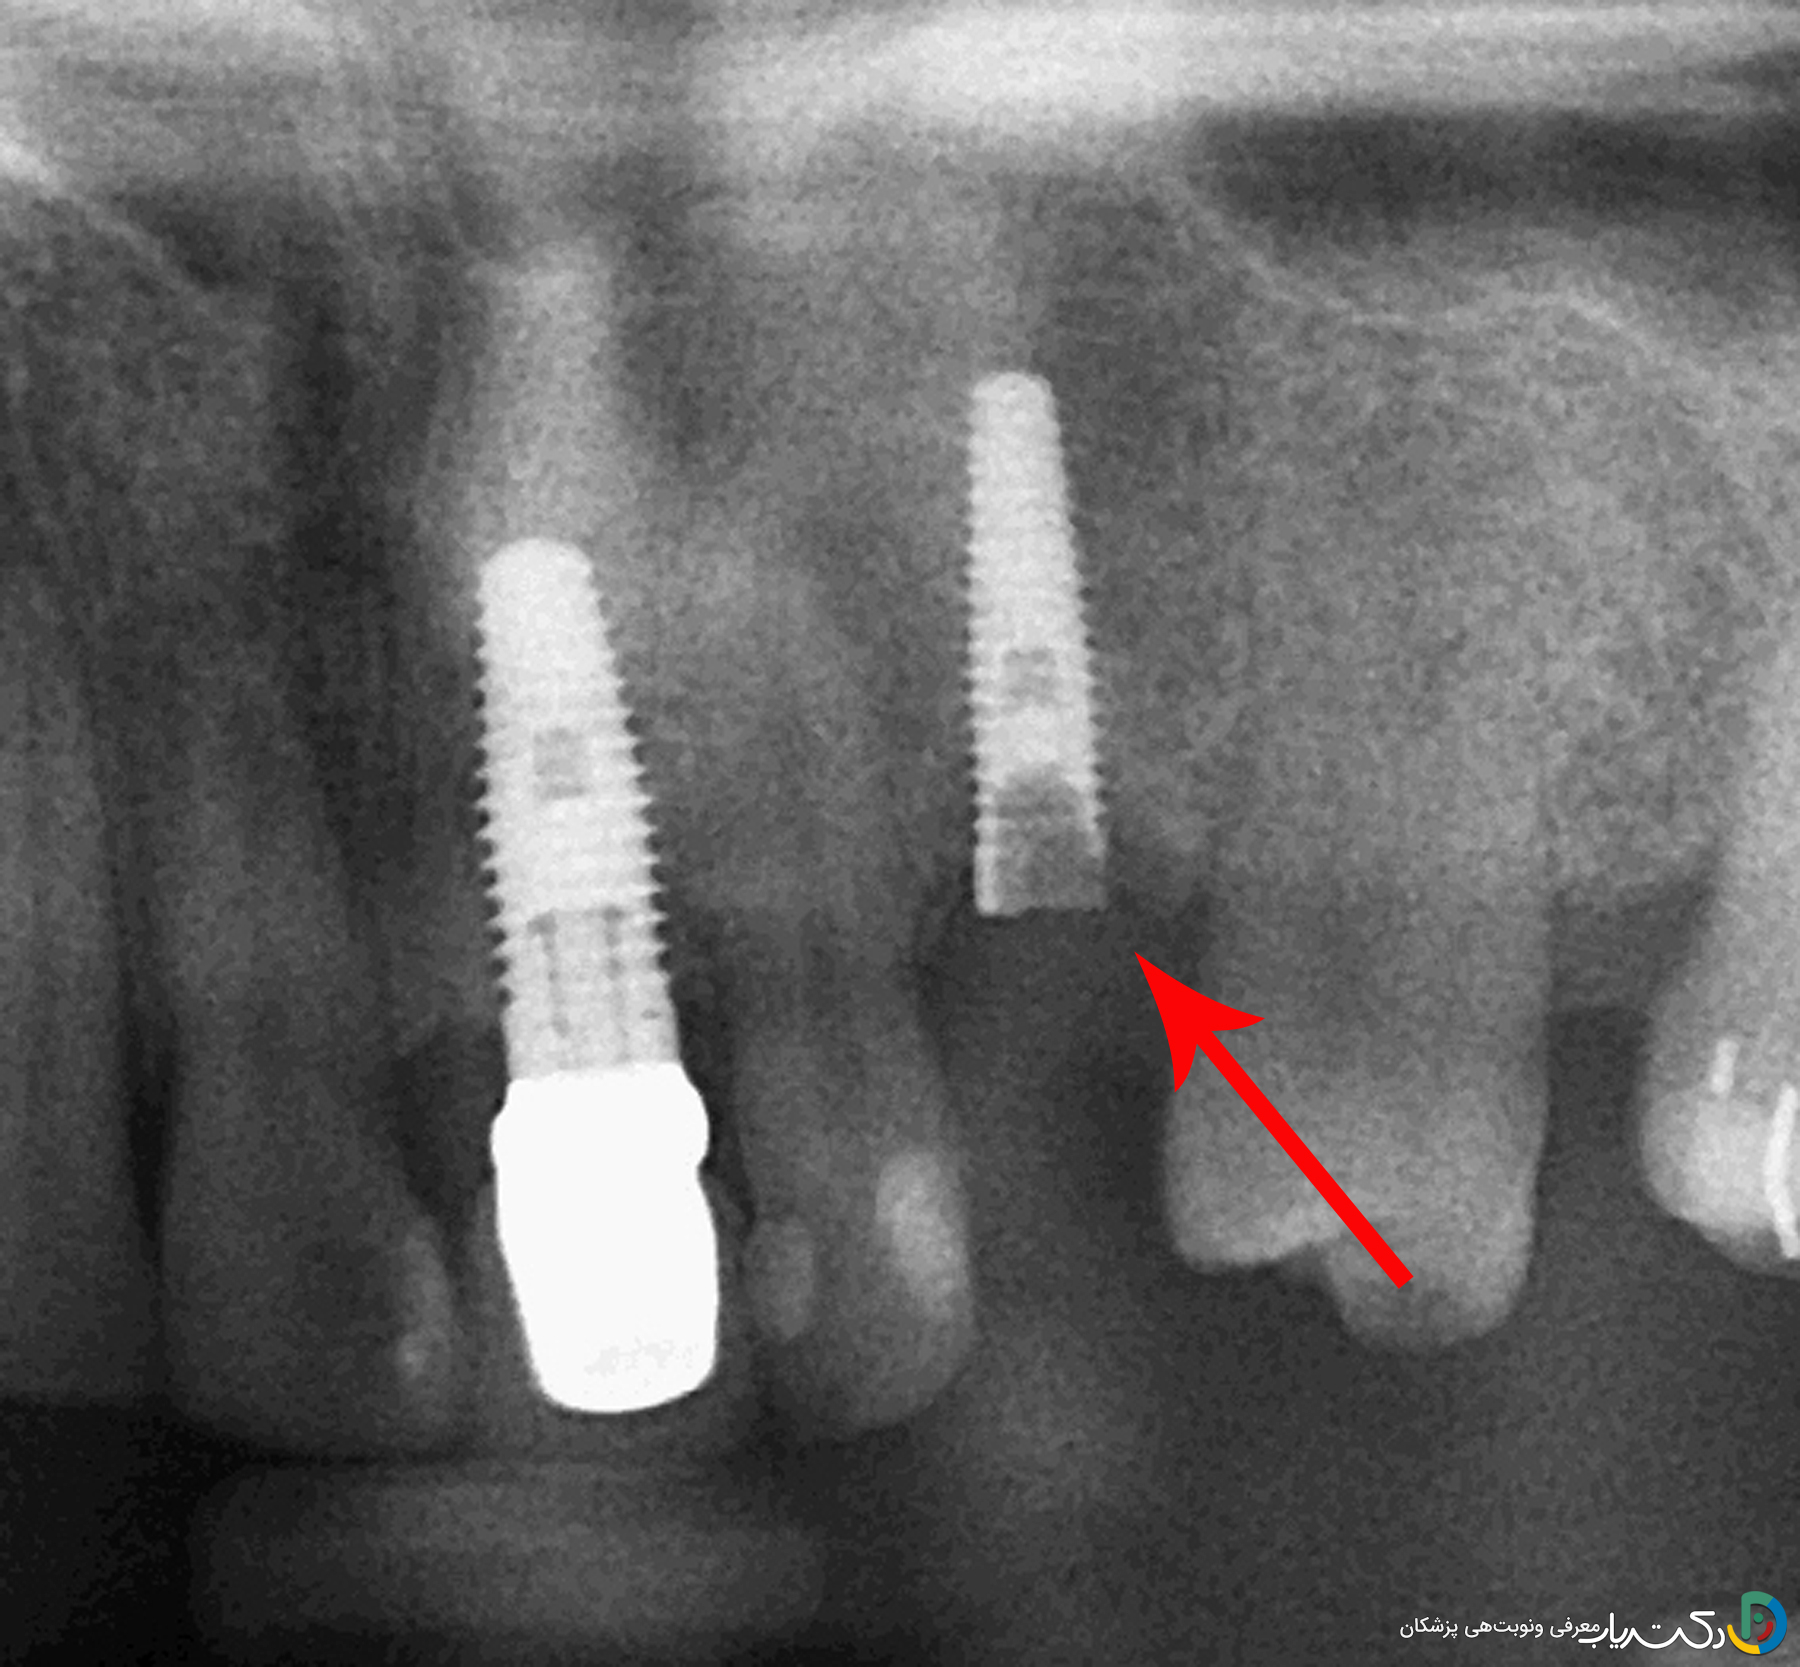

- تعیین دقیق محل شکستگی با رادیوگرافی: یک عکس رادیوگرافی باکیفیت (معمولاً از نوع پریاپیکال) اطلاعات حیاتی زیر را در اختیار دندانپزشک قرار میدهد:

- عمق شکستگی: آیا قطعه شکسته در سطح و قابل دسترس است یا در عمق کانال داخلی ایمپلنت قرار دارد؟

- سلامت رزوههای داخلی ایمپلنت: آیا در اثر شکستگی، به رزوههای داخلی فیکسچر آسیبی وارد شده است یا خیر؟

- وضعیت استخوان اطراف: بررسی سلامت استخوان مجاور ایمپلنت برای اطمینان از عدم وجود تحلیل استخوان.

این اطلاعات به دندانپزشک کمک میکند تا بهترین و کمتهاجمیترین روش را برای خارج کردن پیچ انتخاب کند.